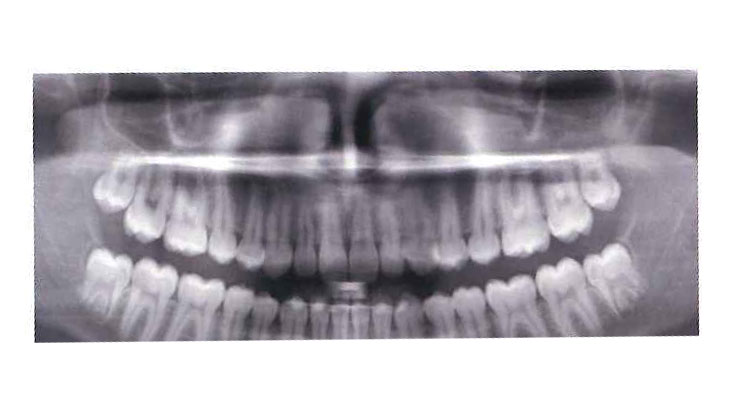

Extraction of Wisdom Teeth

The extraction of wisdom teeth is a procedure to remove one or more wisdom teeth, the four permanent adult teeth in the back corners of the top and bottom of your mouth. Most people have these teeth removed for a number of reasons including pain, discomfort, inflammation, infection or causing damage to neighboring teeth. The surgery is the removal of gum tissue that covers the tooth, detaching the connective tissue that is between the tooth and the bone and finally, removing the tooth and suturing the gum line.